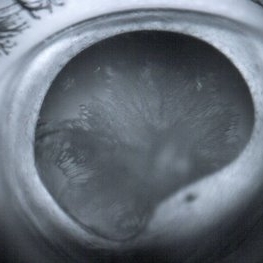

Choroidal Detachment

Sep 10 2014 by Mehul A Shah

A male patient 5-years-old presented to outdoor and found to have retinal detachment with choroidal detachment following blunt trauma

Photographer: Drashti Netralaya,Dahod

Imaging device: FF 450

Condition/keywords: choroidal detachment